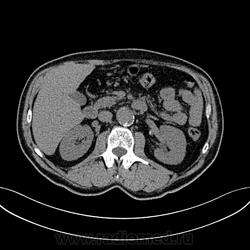

Пациент лежит в кардиологии. Прислали на аортографию. 2 врача УЗИ несколько разошлись в диагнозах: одна видит тромбированную аневризму брюшной аорты, другая - тромбоз нижней полой вены.

А мы получили вот такие красивые картинки.

Шикарно! Тромбированная аневризма инфраренального отдела (над бифуркацией), бифуркации и общих подвздошных артерий, синдром Лериша справа.

И еще маленькая аневризмочка наружной подвздошной слева. Честно говоря, меня больше всего впечатлили коллатерали, благодаря которым клинически он вообще не соответствует исследованию. Конечности теплые, пульсация слабая, но как-то прослеживается...